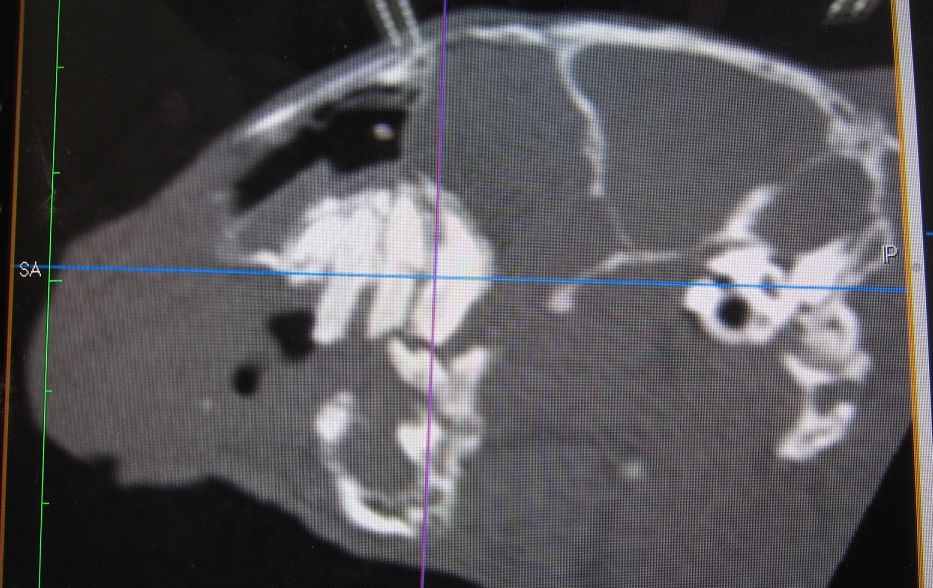

途中経過をCTで

まだまだたくさん残ってますが、👆これが👇こうなります。

完全に取り切れてない部分もありますが、すでに時間もかなりかかっていたのでひとまず終了。